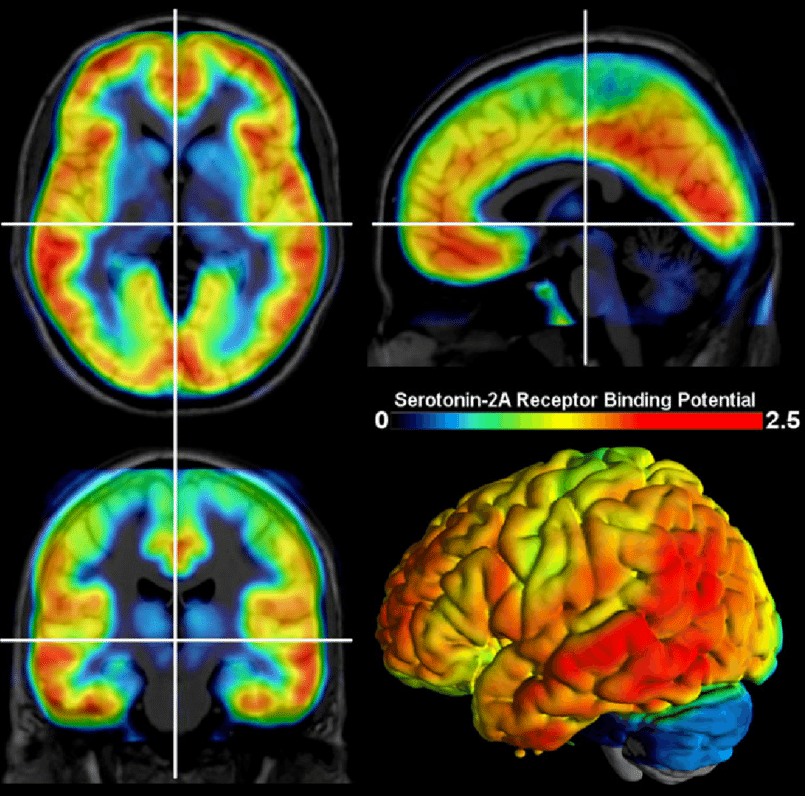

They think psychedelics might fix it ๐Ÿงต Image

Here's what happens in a depressed brain:

The circuits connecting your emotions to your memories start breaking down.

like roads crumbling between two cities.

messages can't get through anymore,

๐˜€๐—ผ ๐˜†๐—ผ๐˜‚ ๐—ด๐—ฒ๐˜ ๐˜€๐˜๐˜‚๐—ฐ๐—ธ ๐—ถ๐—ป ๐—น๐—ผ๐—ผ๐—ฝ๐˜€. Image